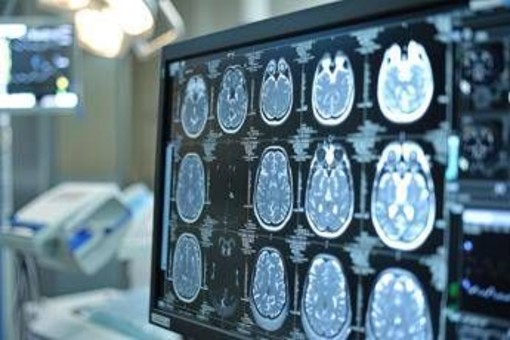

Asundexian ha ottenuto la designazione fast track dalla Food and Drug Administration degli Stati Uniti come potenziale trattamento per la prevenzione dell'ictus nei pazienti con ictus ischemico non cardioembolico, ricorda la nota. Tuttavia - si legge - va sottolineato che asundexian è ancora un farmaco sperimentale e non è stato ancora approvato da alcuna autorità sanitaria. Lo studio Oceanic-Stroke ha analizzato efficacia e sicurezza di asundexian, inibitore orale del Fattore XIa, somministrato alla dose di 50 mg una volta al giorno, per la prevenzione dell'ictus ischemico in pazienti che avevano recentemente avuto un ictus ischemico non cardioembolico o un attacco ischemico transitorio (Tia) ad alto rischio. Il trattamento è stato valutato in combinazione con la terapia antipiastrinica standard. Si tratta di uno studio multicentrico e internazionale, randomizzato, controllato con placebo, in doppio cieco, a gruppi paralleli e guidato dal numero di eventi, che ha arruolato oltre 12.300 pazienti.